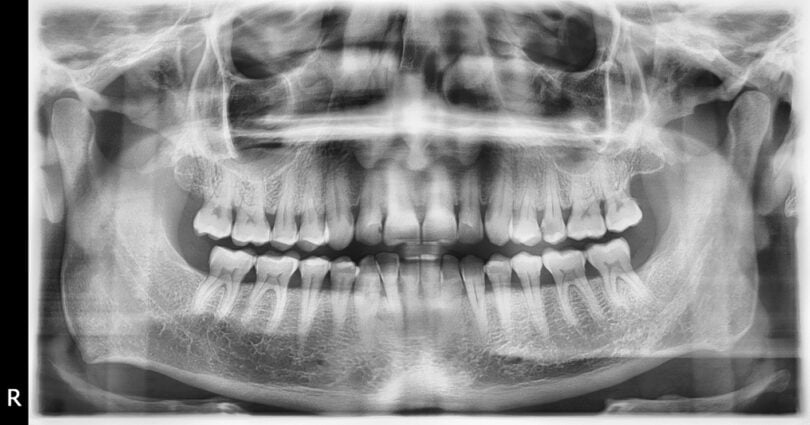

Os algoritmos são o resultado de uma extensa base de dados que “treinou” o software, através de um grande conjunto de dados de radiografias dentárias, incluindo imagens panorâmicas e de oclusão. Assim, médicos dentistas de todo o mundo identificaram dezenas de milhares de alterações patológicas e vestígios de tratamentos dentários anteriores nas radiografias. Os dados foram “carregados” nas redes neurais artificiais, permitindo-lhes distinguir entre diferentes descobertas, tais como cáries, infeções e preenchimentos de canais radiculares.